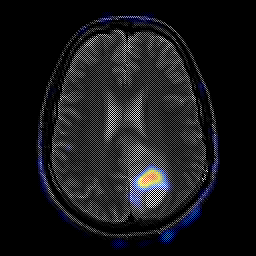

glioma overlay -- Slice #18

[Home][Help][Clinical] Slice 18